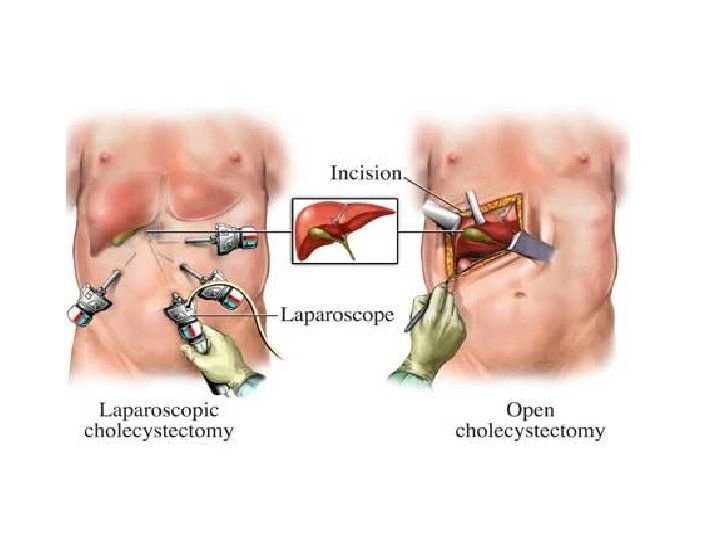

• Rehidrim me perfuzione (glukoze 5%, Na. Cl 0. 9%, ringer) per te siguruar volumin e qarkullimit, diurezen dhe sasine e nevojshme te kalorive. • Spazmolitik? !- per te qetesuar dhimbjen abdominale • Antibiotike (ceftriakson+metronidazol): doza percaktohet nga shkalla e procesit inflamator dhe mosha e pacientit. • Pacienti duhet te mbahet nen vezhgim • Kirurgji